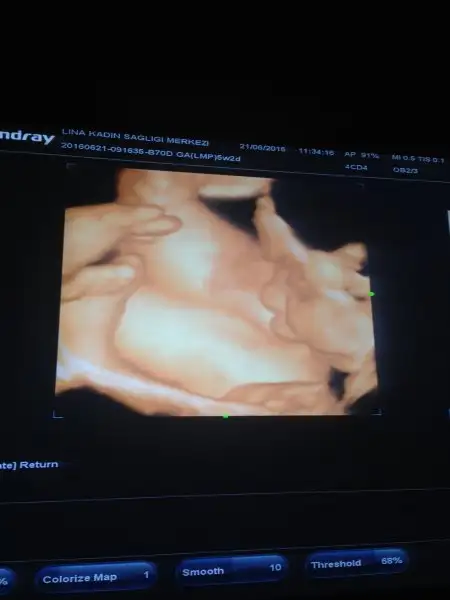

Maşallah diyelim teyzeleri :) bizim kızımızda biraz Tonbiş doktorum dana diye seviyor 31 haftalikken 2 kg idi 42 cm boyu da. Şekerden şüphelendiler ama sukur onunla ilgili değilmiş sanirim benim fazla meyve yememden oluyor. Böbreğinde de sağda buyume var Dedi bakalım bir daha kı gidişimize insallah azalma olmustur. O resimde de bacağını emiyordu yavrum :) Rabbim hepimizin hayirlisiyla kucağına almayı nasip etsin